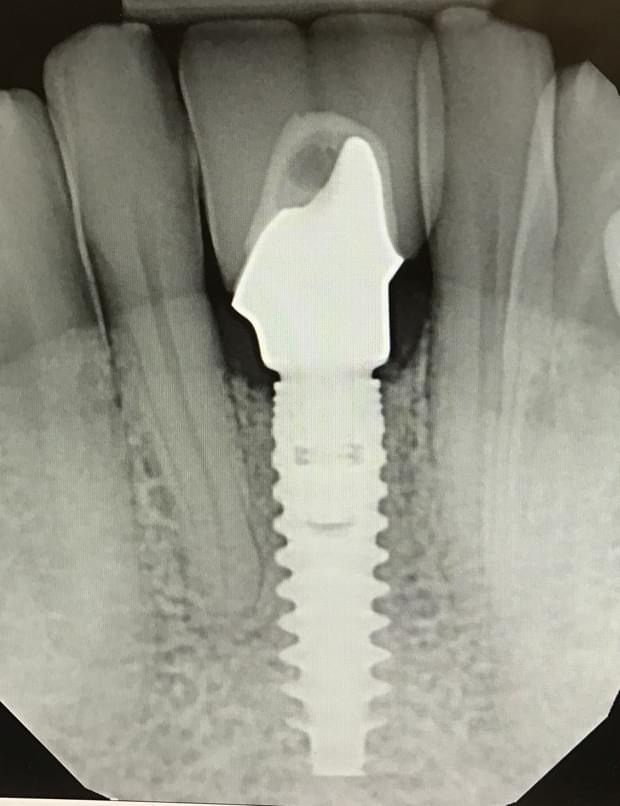

Single Implant Replacing two missing front teeth:

Single Implants replacing two Front teeth